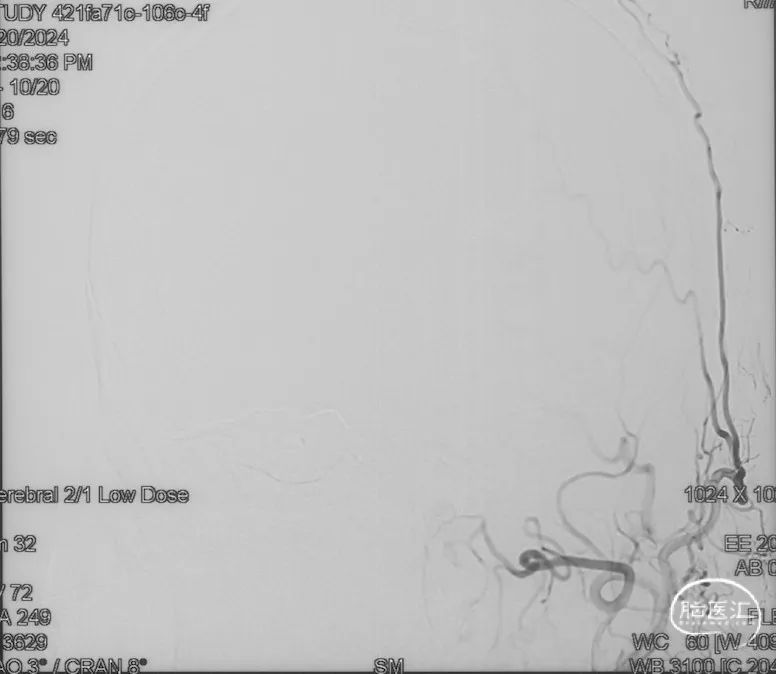

影像学的随访

术后9m

右侧颈内动脉造影未见瘘口显影及静脉早显

右侧颈外动脉造影未见瘘口显影及静脉早显

左侧椎动脉造影未见瘘口显影及静脉早显